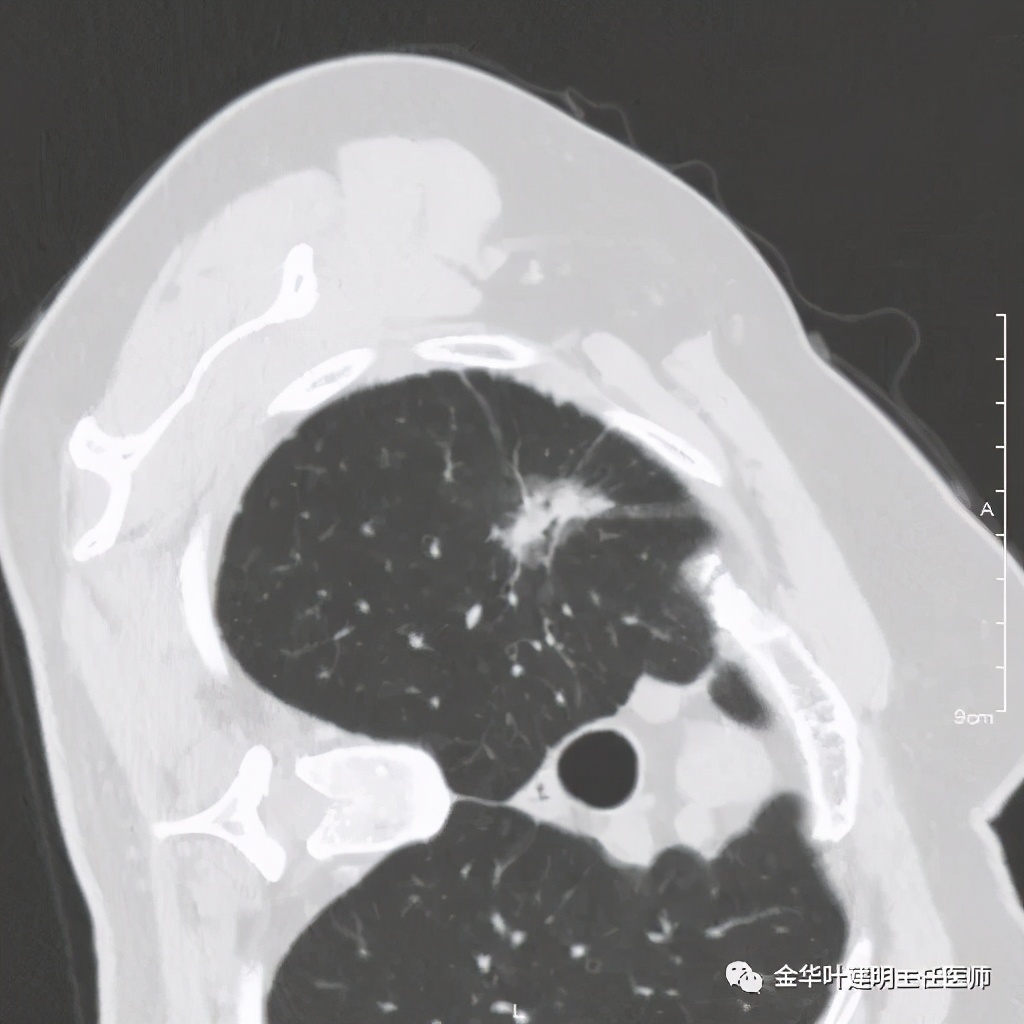

六、神经内分泌癌(此例为不典型类癌,小细胞癌以后再总结):

影像特征:不典型类癌一般圆形生长,实性,边缘比较光滑,但硬度不够。侵蚀力也不够。就像这例,我们发现其与肺动脉接触的地方,居然无法推压血管,反而肿瘤被血管占据了其生长的位置,在支气管内,肿瘤也是对支气管壁没有造成明显的破坏。也就是说 圆形边清较软、侵蚀力弱的实性结节 要考虑类癌的可能性。